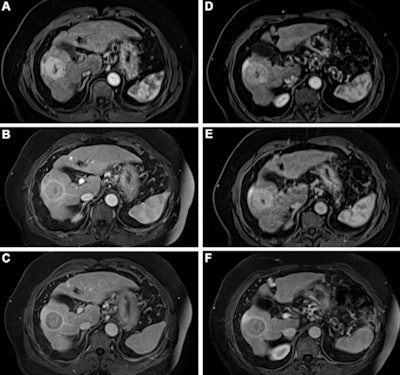

Contrast-enhanced MRI of the liver after administration of gadopiclenol (0.05 mmol/kg) and gadobutrol (0.1 mmol/kg). Axial 3D T1-weighted dynamic contrast-enhanced MRI scans during the (A, D) arterial, (B, E) portal venous, and (C, F) delayed phases in a 66-year-old man with hepatocellular cancer. Images were obtained after administration of gadopiclenol at 0.05 mmol/kg (in A, B, and C) or gadobutrol at 0.1 mmol/kg (in D, E, and F). Images and caption courtesy of the RSNA.The investigators found that gadopiclenol at half the dose of gadobutrol performed comparably for all qualitative visualization parameters and for all readers. The majority of readers across the three groups (ranging from 75% to 83%) reported no preference between the two agents for image quality.